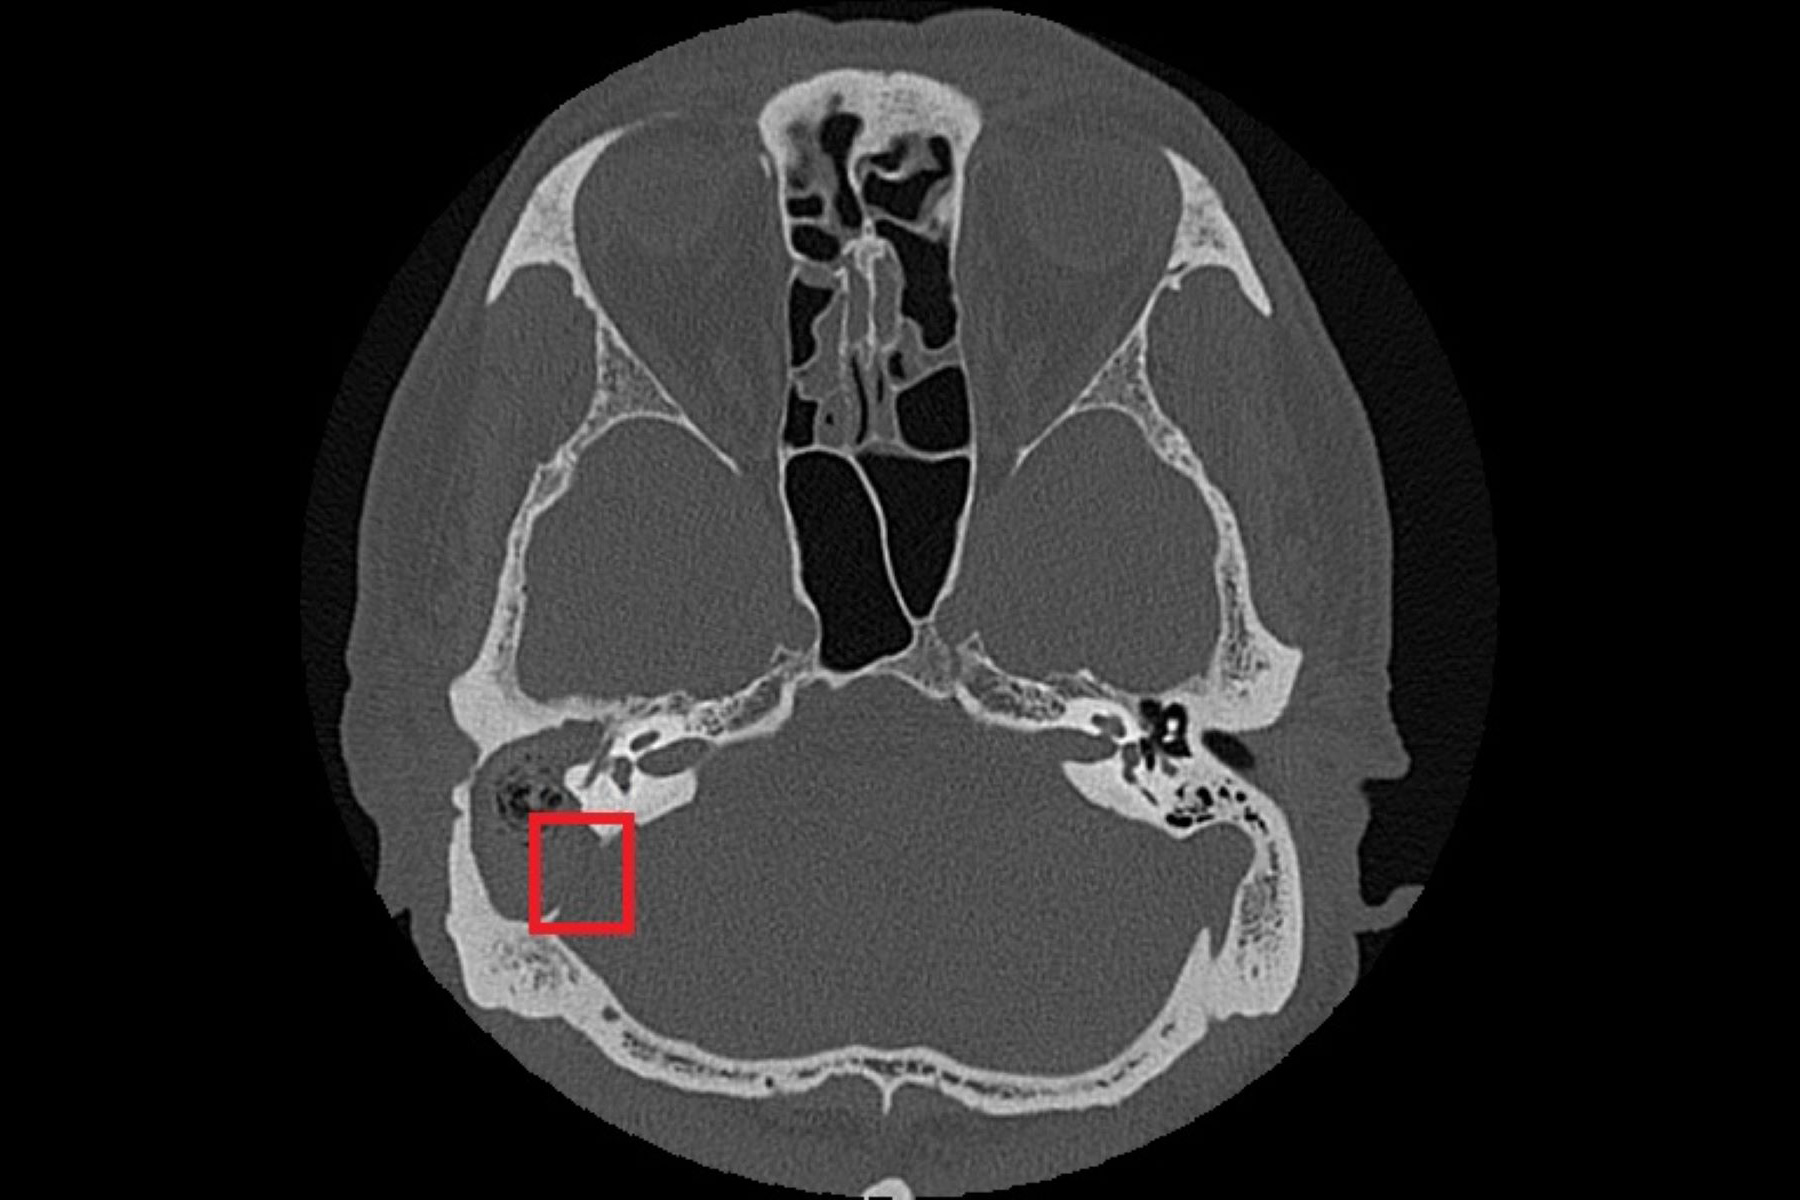

耳鼻喉科鄭靜雯醫師在進行局部清理及藥物治療後,症狀仍未明顯改善,後續更出現右側顏面神經麻痺。經顳骨電腦斷層檢查確認為慢性中耳炎併發膽脂瘤,且病灶已侵蝕顱底骨質,需安排住院治療。期間,張先生先後接受抗生素及局部治療控制感染,並經歷鼓室重建術、乳突鑿開術清除膽脂瘤病灶及修補耳膜、外耳道成形術及顱底缺損修補,術後恢復良好,顏面神經功能也完全恢復。

由於膽脂瘤多發生在中耳或接近顱底的位置,一旦形成,可能影響聽力與神經功能,其分泌物亦容易滋生細菌,導致反覆感染;若未及時治療,可能引發暈眩,甚至因鄰近顱內而造成腦膜炎、腦炎或腦膿瘍。目前,手術切除是膽脂瘤根治的唯一方法,術前需以顳骨電腦斷層檢查評估膽脂瘤範圍及侵蝕程度;手術方式依病灶大小、位置,可能採耳內微創、耳前或耳後切開術,徹底清除膽脂瘤並重建受損結構。急性發炎期則需輔以抗生素控制感染,術後追蹤可降低復發風險,但膽脂瘤若已侵蝕骨質,仍需長期觀察。以張先生為例,雖前後接受過局部藥物、抗生素治療,但考量其慢性中耳炎併發膽脂瘤已破壞聽小骨、乳突及部分顱底骨質,因此需從耳後切開進入外耳道及中耳腔,打開耳後的乳突骨,將病變組織除去後,重建修復骨骼和軟組織缺口。